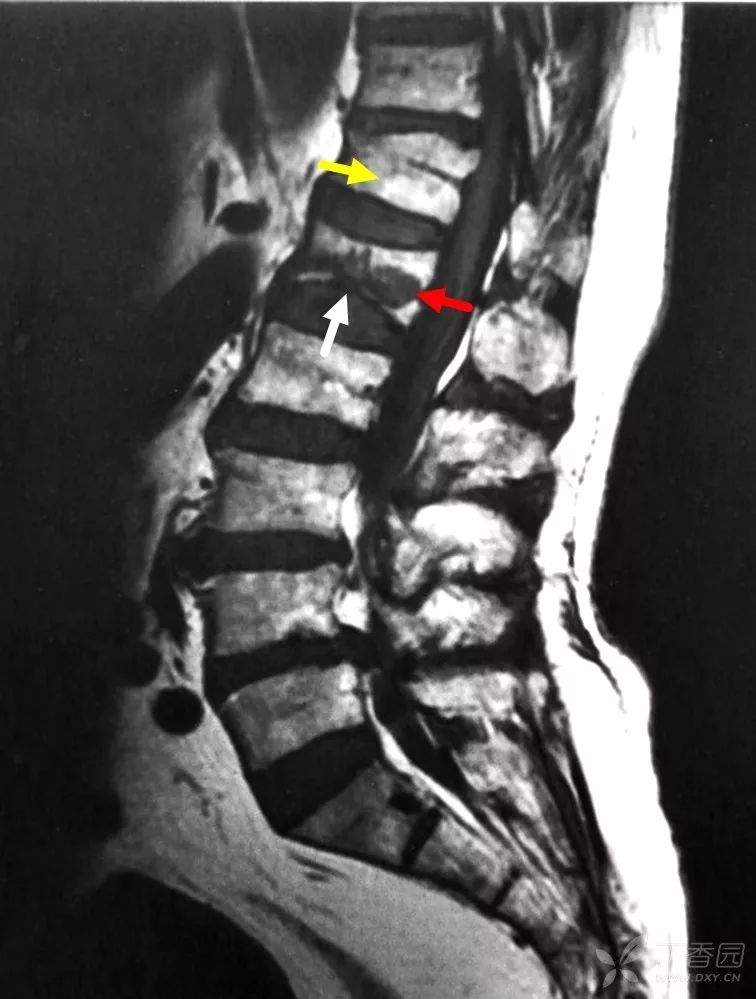

图示:腰 1 椎体下部终板中部断裂(白箭),椎体中、后部见低信号区(红箭),胸 12 椎体的高信号符合脂肪充填的骨髓窦(黄箭)。

这个病例诊断椎体骨质疏松性压缩性骨折是没有异议的,从核磁和 CT 看,腰 1 椎体作为新鲜骨折责任椎体也是没有异议的,但是具体在手术判断时还是容易出错。